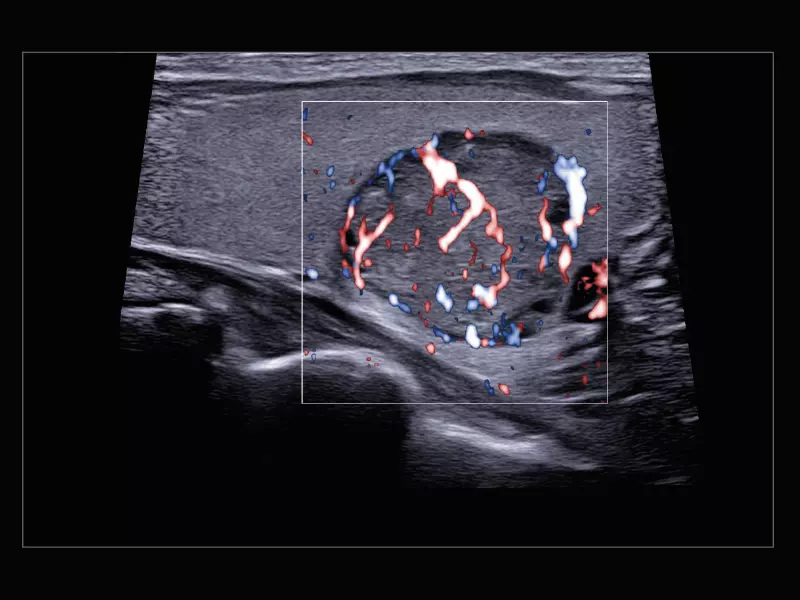

MyLab™9 Platform - High resolution imaging in testis

MyLab™9 Platform - High resolution imaging in testis